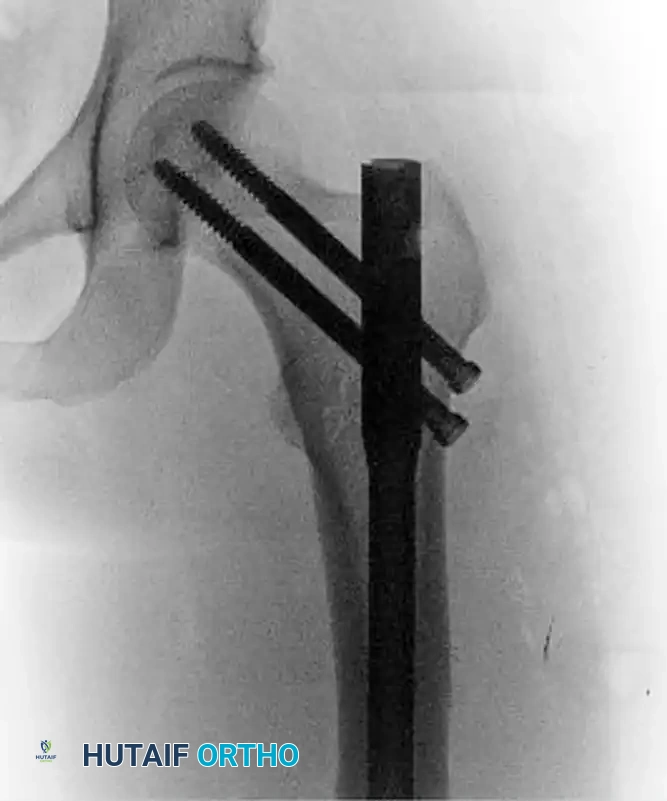

Image

Postoperative anteroposterior radiograph following successful fixation with an antegrade intramedullary nail locked in reconstruction mode.